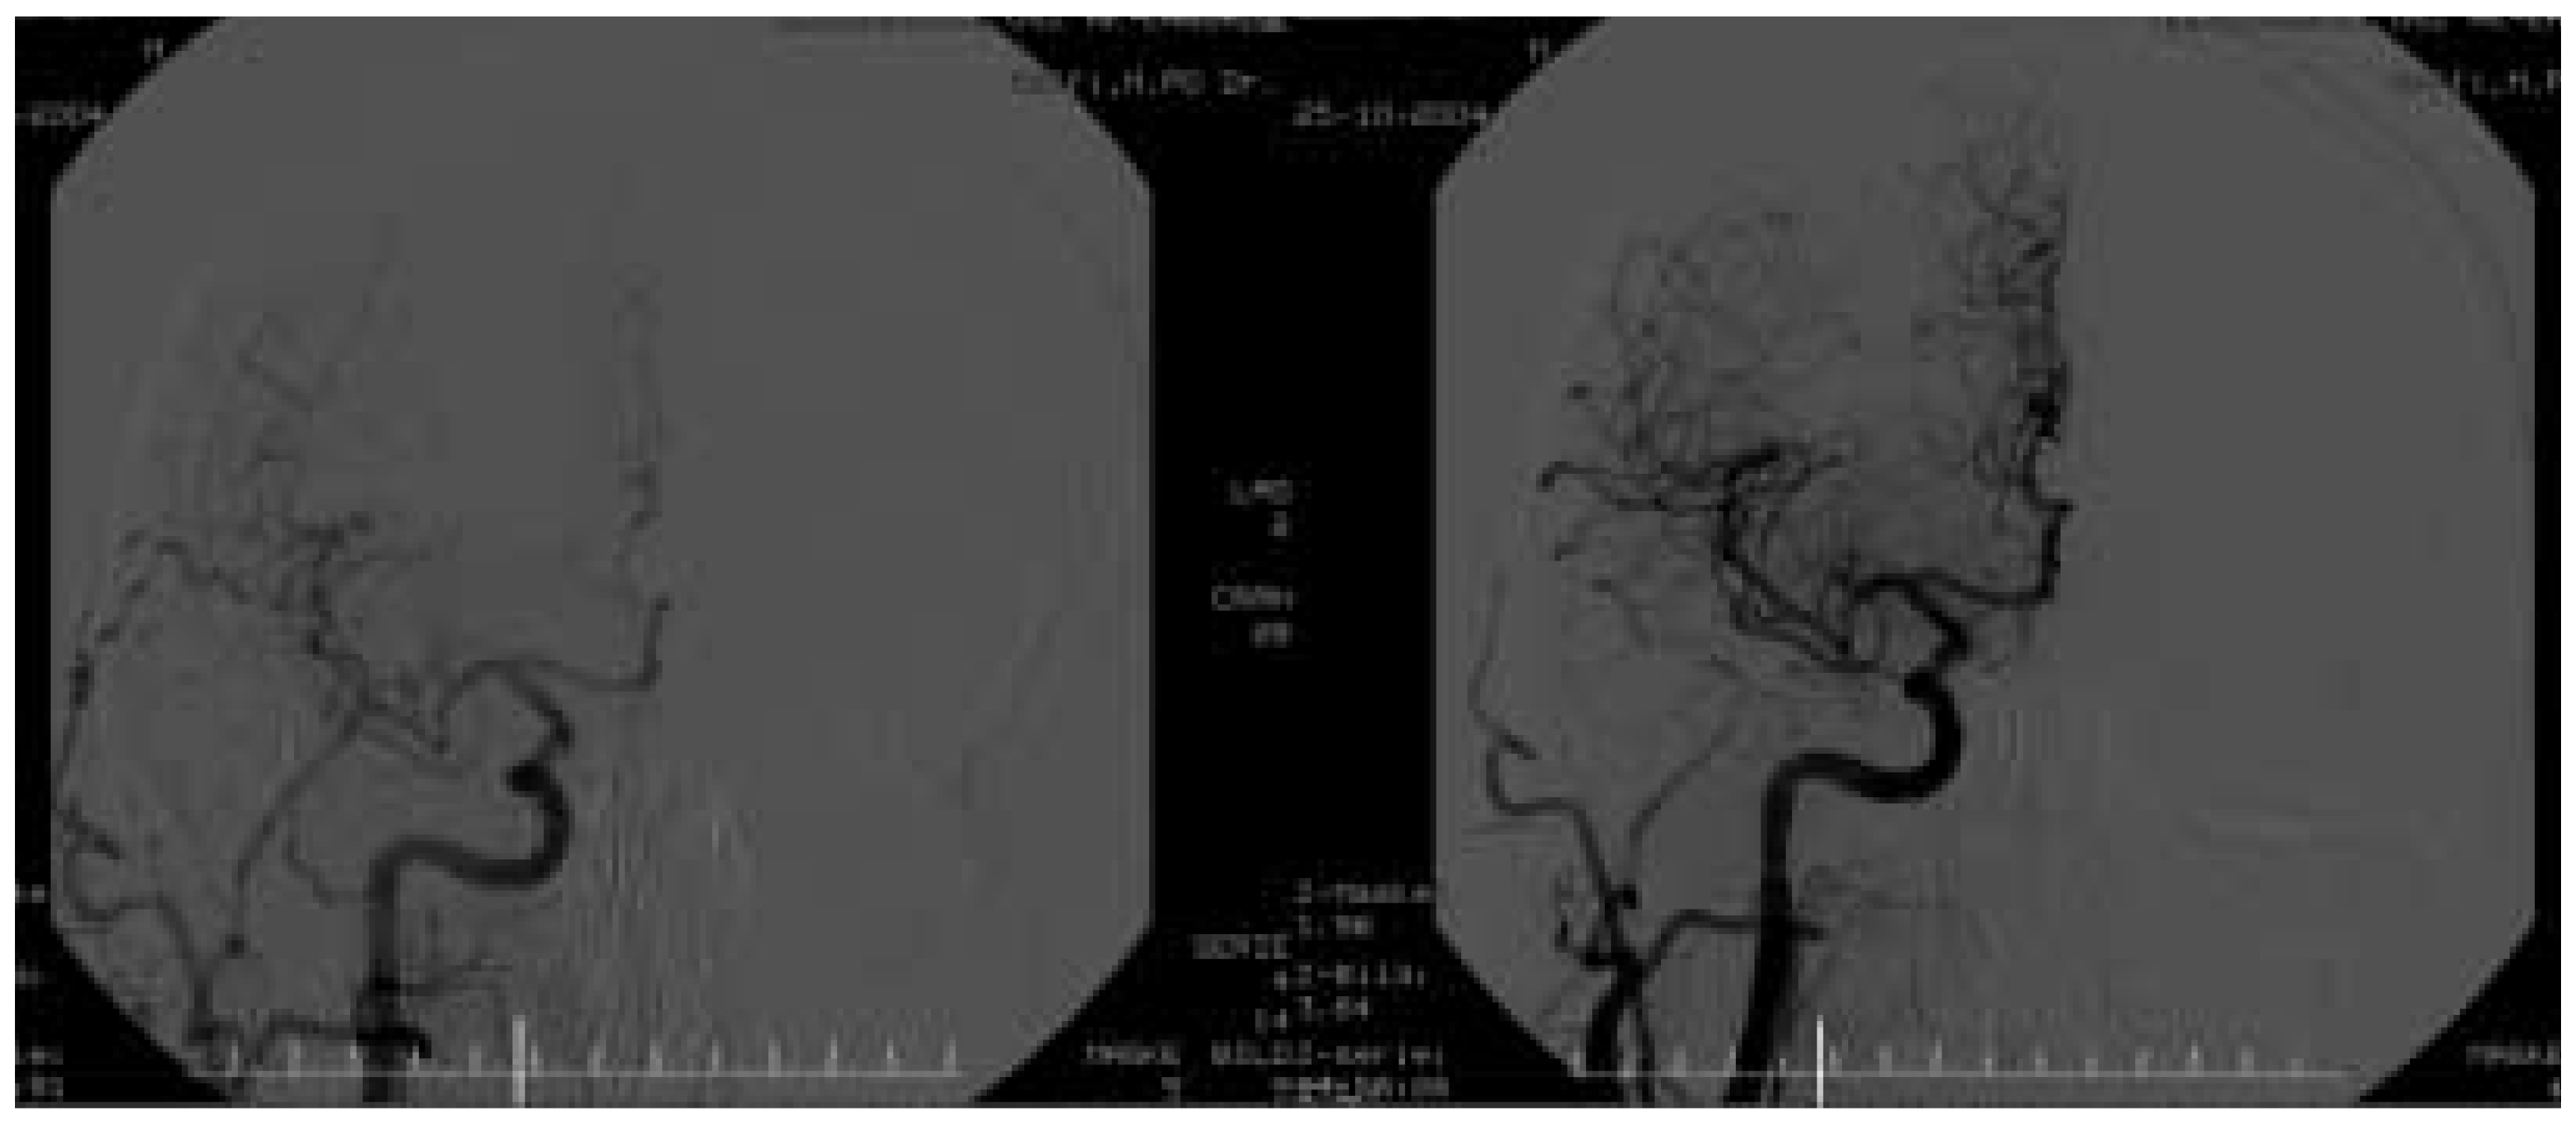

Man schätzt, dass bis 1999 ungefähr 3000 perkutane Eingriffe an den Karotiden weltweit durchgeführt wurden. Zunächst wurden nur Dilatationen mit Ballon-Kathetern durchgeführt, im Verlauf ersetzte die Stent-Einlage aufgrund der besseren Resultate, die reine Ballon-Angioplastie. Vom Jahr 2000 an nahm die Anzahl der perkutanen Karotis-Interventionen exponentiell zu. Man schätzt, dass 2003 lediglich in den USA ca. 15000 Karotis-Stenting-Eingriffe durchgeführt wurden (ungefähr 10% aller Endarterektomien). Die rasche Zunahme der Fallzahlen hat mehrere Erklärungen: die zunehmende Erfahrung der Interventionalisten, die optimierte plättchenhemmende Therapie (Aspirin und Clopidogrel) und die technischen Fortschritte im Materialwesen (Katheter, Ballone und insbesondere Embolieprotektionssysteme). Der Eingriff wird, ähnlich wie bei der Herzkatheteruntersuchung, durch einen femoralen arteriellen Zugang in Lokalanästhesie durchgeführt. Mittels Digitalsubstraktionsangiographie werden vor und nach dem Eingriff die Verhältnisse sowohl lokal (Abb. 1) als auch intrakraniell (Abb. 2) erfasst. Distale Embolieprotektionssysteme (Abb. 3, 4), welche die Inzidenz von neurologischen Ereignissen beim Karotis-Stenting signifikant reduziert haben [14, 15], sollten konsequent gebraucht werden. Der Patient wird postinterventionell neurologisch und hämodynamisch überwacht und meistens am nächsten Tag entlassen. Die nötigen prä- und postinterventionellen Massnahmen / Untersuchungen sind in Tabelle 1 zusammengefasst. Im Gegensatz zu den Koronareingriffen ist die Restenose nach Stenting der Karotis selten (4–7%) [16].

Abbildung 1. Digital-Subtraktionsangiographie einer schweren Stenose der Carotis interna vor (links) und nach (rechts) Karotis-Stenting.